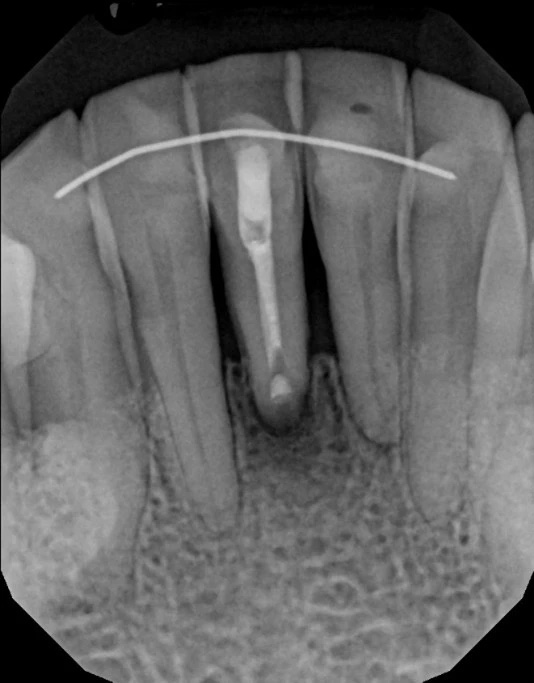

Symptoms that may prompt evaluation include lingering or recurrent pain, swelling, a draining sinus tract, or radiographic evidence of a radiolucency at the root apex. However, some troublesome lesions are discovered incidentally on routine imaging; lack of symptoms does not always mean absence of disease. Advanced imaging such as cone beam CT (CBCT) provides a three-dimensional view that helps clinicians determine whether apicoectomy is technically feasible and likely to be successful.

Cone beam CT provides a three-dimensional view of the tooth, surrounding bone, and nearby anatomical structures, enabling more precise diagnosis and surgical planning. CBCT can reveal canal morphology, root fractures, the extent of periapical lesions, and relationships to critical structures such as sinuses or nerves. This detailed information helps clinicians assess whether a retrograde approach is feasible and what surgical access will be required.

Using CBCT reduces uncertainty during case selection and supports microsurgical strategies that minimize bone removal and protect adjacent anatomy. The technology improves communication with patients by showing the problem in three dimensions and explaining why a particular course of care is recommended. Ultimately, CBCT contributes to more predictable outcomes and tailored treatment plans.